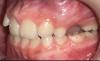

Девочки,сняли сегодня аппарат Марко Росса. Результат за пол года . Теперь весной брекеты ,либо элайнеры 2*4,либо ждем смены Зубов и ставим полноценные на весь рот ,будет понятно после КТ в феврале. Результатом на данный момент мы очень довольны 👍 фото в коментах) первые фото ДО,рядом после.